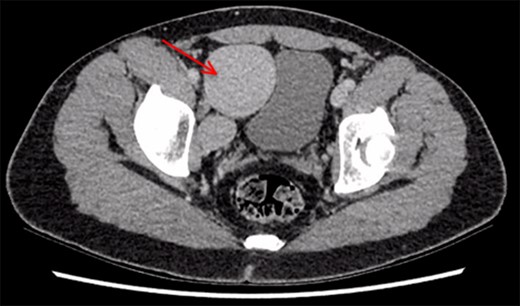

A 26-year-old man was referred to our vascular surgery tertiary referral service from his local hospital with leg size discrepancy (right > left) and prominent right leg varicose veins distally. He had lower urinary tract symptoms (frequency >30 times per day) for a year prior to presentation but had no leg symptoms in relation to his varicosities. His past medical history was of premature birth, as one of triplets, who spent a prolonged period on a neonatal intensive care unit. The patient thought he may have had a deep vein thrombosis in his right leg as a child. An MRI of his right thigh and pelvis demonstrated a 5 cm venous aneurysm (EIV), indenting the bladder, and generalized distal venous dilatation of both deep and superficial veins. He subsequently underwent venography, which confirmed an aneurysmal EIV, with massive collateral dilatation of trans-pelvic veins and complete occlusion of the right common femoral vein (CFV). A concurrent attempt at endovenous stenting was made, but was unsuccessful as the CFV could not be passed with a guide-wire and no alternate route was found possible. Further characterization by CT demonstrated a dilated and tortuous right internal iliac vein (IIV) feeding the aneurysm (Fig. 1). A multidisciplinary decision was made to proceed to operative repair, in light of the patient’s debilitating urinary frequency from the mass effect of the aneurysm. Pre-intervention venous severity scoring was not pursued as the patient’s symptoms were only bladder-related. The patient underwent an open aneurysmectomy via a Rutherford-Morrison incision, with concurrent right retrograde ureteric stent placement. Intra-operatively, a wide-necked aneurysm was confirmed to arise from the EIV (Fig. 2) in a saccular fashion. The aneurysm was clamped at the neck and closed with 3-0 Prolene (Ethicon, Inc., New Jersey, USA) leaving a normal calibre EIV (Figs 3 and 4). The IIV remained patent at the end of the procedure and a venous bypass was not performed. The patient recovered well post-operatively and was discharged home four days later, with removal of the ureteric stent prior to discharge. He has been followed up 6-monthly since and remains well at 2 years’ post-operatively. CT venogram has shown a good post-operative result, with no residual aneurysm (Fig. 5). The patient’s pre-operative lower urinary tract symptoms have improved. He did not develop any leg symptoms.

CT scan demonstrating right iliac vein aneurysm (5.7 cm) (red arrow) compressing the patient’s full bladder.